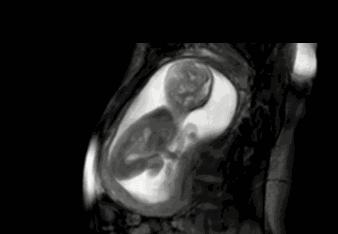

等到他再大点的时候,“蛙泳”项目已经无法进行了,但是你以为他长大点了就会听话、懂事,当个乖宝宝吗?

咦?这地儿怎么越来越小了,不管,我挤,我顶......